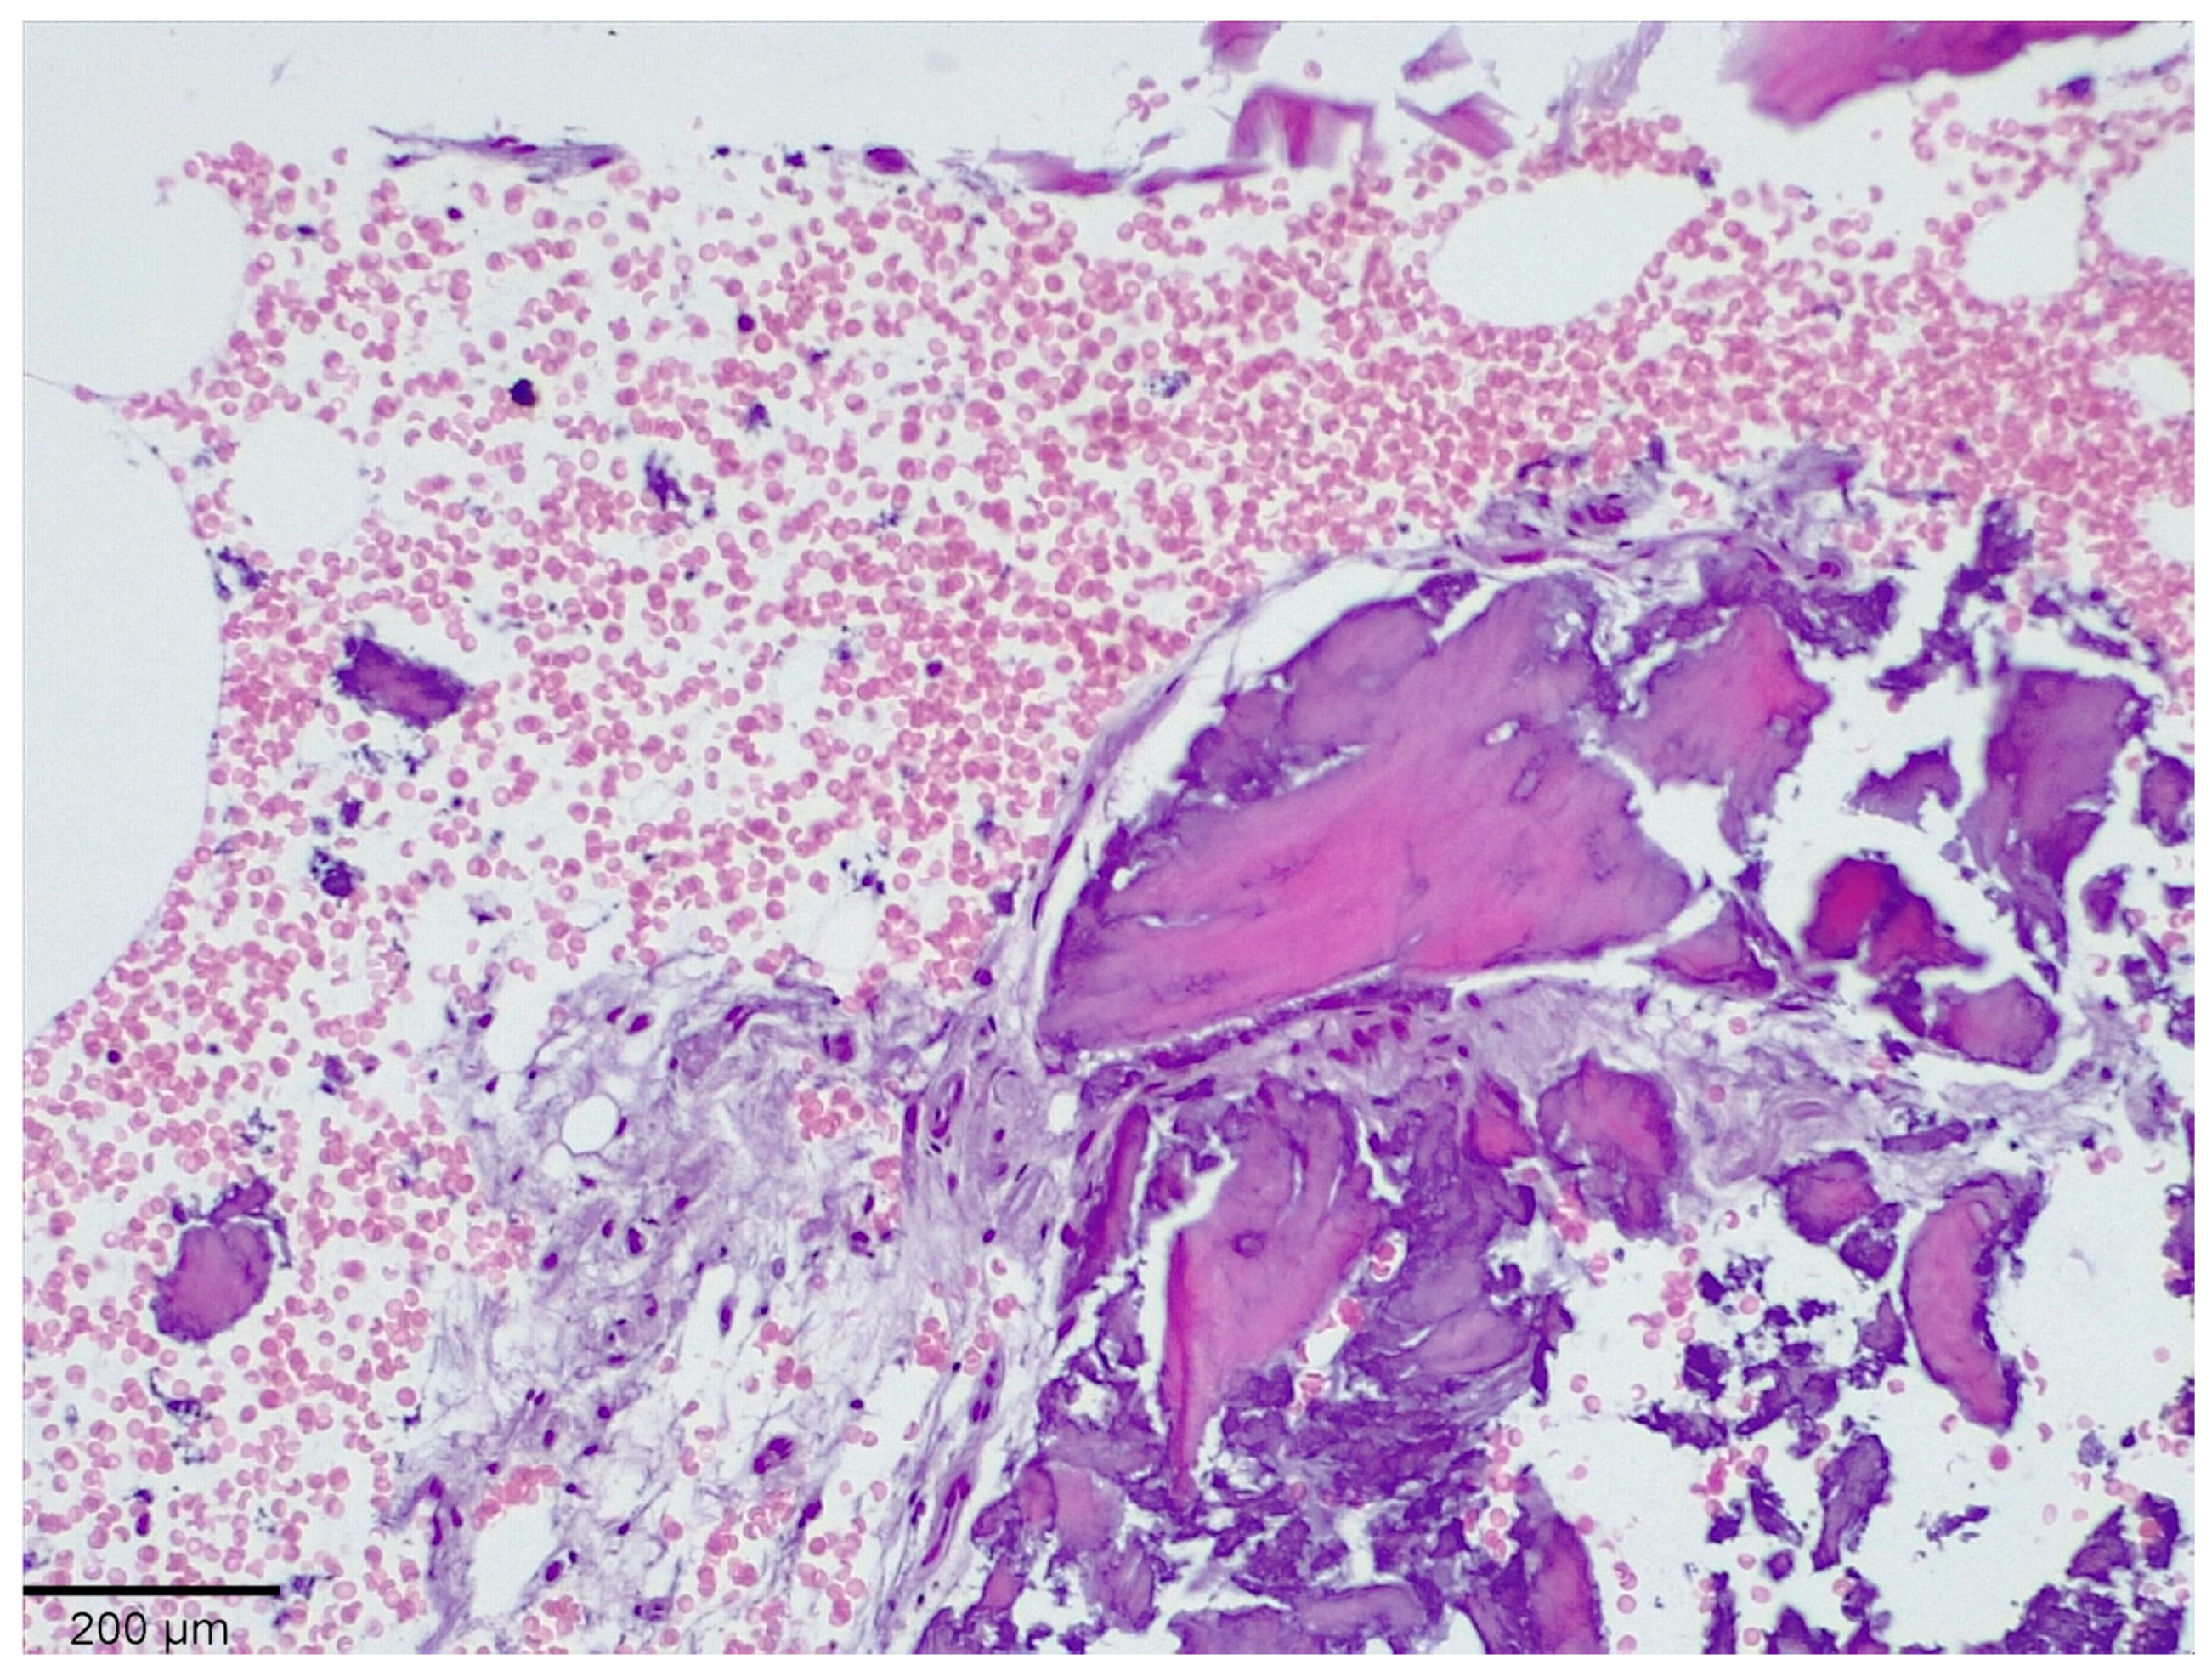

3.1. Histological Analysis Showed Signs of New Bone Formation at 60 Days

3.2. Histologic Data Obtained after Samples Analysis at 24 Months of Evaluation

| New bone | 16.3 ± 1.98 | 41.1 ± 0.76 | 54.5 ± 0.24 | 59.4 ± 1.23 * |

| Residual Graft | 37.1 ± 0.34 | 30.0 ± 0.45 | 21.3 ± 0.88 | 15.6 ± 086 |

| Connective tissue | 46.6 ± 0.11 | 29.9 ± 0.56 | 24.2 ± 0.32 | 25.0 ± 0.44 |